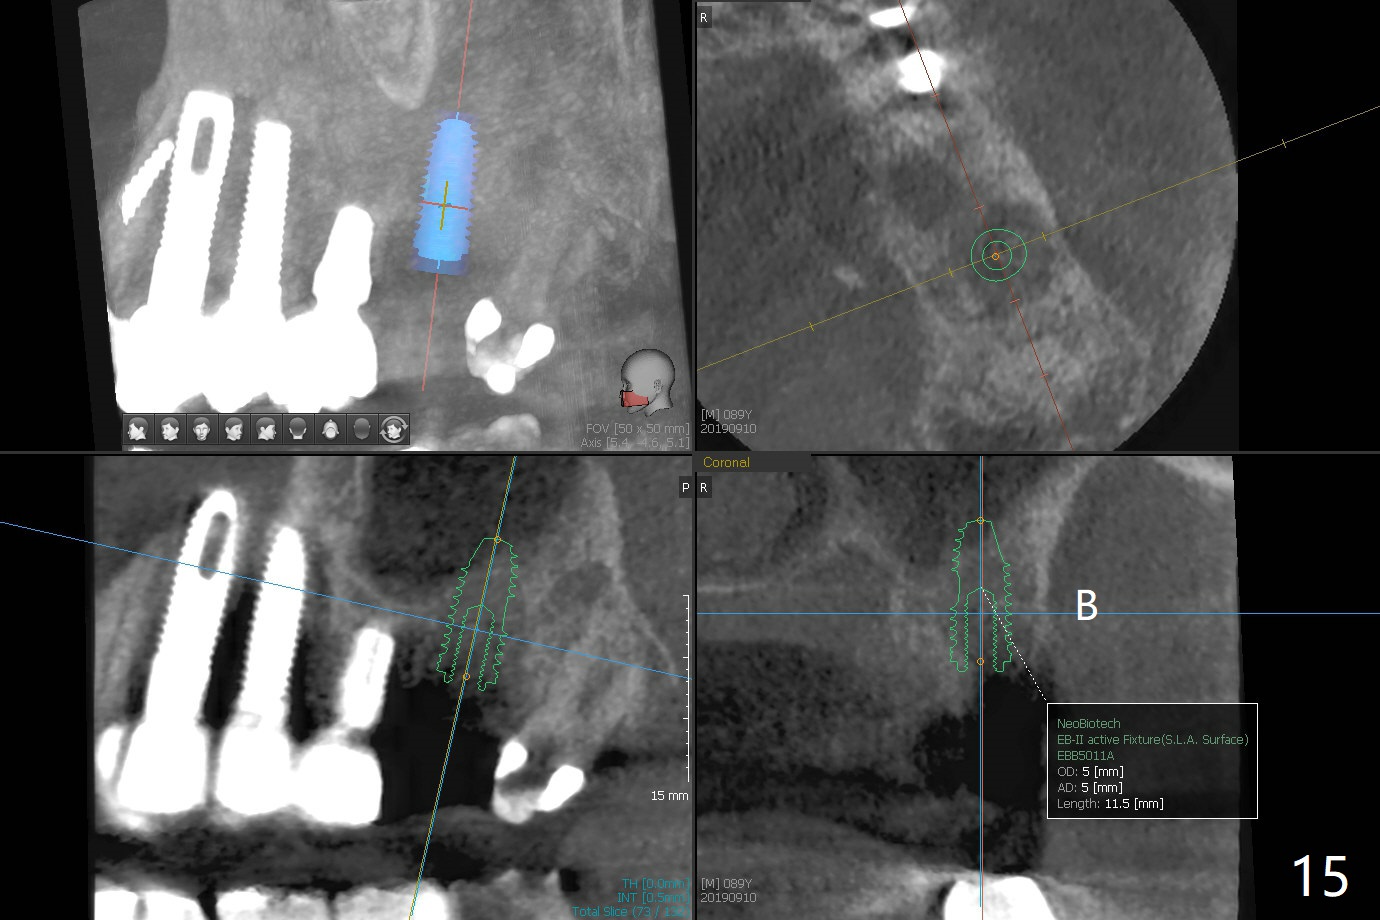

The 7x14 mm implant at #15 of a 89-year-old man is found to be loose ~ 1 year post cementation (Fig.1). After implant removal and debridement, bone graft is placed (Fig.2 G); the mesiocervical caries of the 3rd molar is removed, but not filled (*). With collagen membrane fixed with Chromic gut suture (Fig.3), setting acrylic is applied in the edentulous area, including the mesiocervical cavitation of the 3rd molar (Fig.4) for further retention. Bone graft gets lost following socket preservation at #31 with periodontal dressing. When the bone graft matures, a new implant (Fig.6 green) will get primary stability from the native bone, i.e., coronal to the sinus floor (Fig.5 F). The acrylic dressing (Fig.7 A) with a portion locking to the undercut of the neighboring crown (*) remains in place 5 weeks postop. When the dressing is cut off, the bone graft is exposed with odor (Fig.8,9 *). Periodontal dressing is applied. The distolingual portion of it gets lost due to brushing a day later. When he returns, the dressing is removed (Fig.10). It appears that the growing in gingival margin is pushing the bone graft out. A moment later after just a few rounds of swallowing, more graft is lost (Fig.11). We would love to leave the wound open, but the senior citizen complains of air leaking and requests reapplication of periodontal dressing. The bone graft is almost gone when the 2nd periodontal dressing is removed nearly 2 months postop (Fig.12). The tooth sensitivity disappears when MO caries is taken care of. The socket has a dimple 5 months postop (Fig.13), although it is filled with bone graft (Fig.14). Due to low bone density (~500 HU), sinus lift is required for implant stability with PRF (Fig.15). In fact the lab chooses not to do sinus lift.